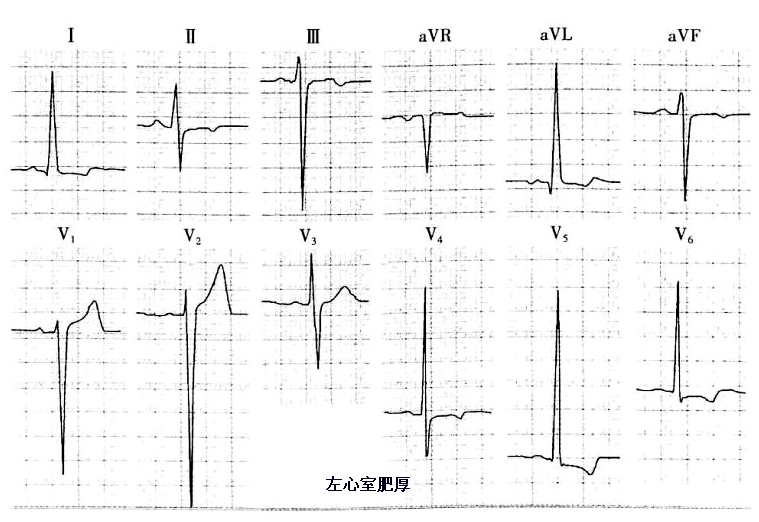

(1)当V1、V2出现高大R波时,表示存在右心室肥厚,当V5、V6出现高大R波时,表示左心室肥厚,具体如下图所示。当然单纯靠这点就判断心室肥厚有点欠妥当,临床还需结合心脏超声和心脏浊音界叩诊。

图12